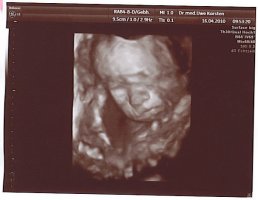

Tolle Fotos hier übrigens. Stelle mal ein paar neue von unserer Kleinen rein. Am Freitag hat sie sich das erste Mal bequemt, ihr Gesicht zu zeigen. Ich war echt fasziniert. Es ist so schön, dass Baby zu sehen. Bin jetzt schon total verliebt. Was soll das erst werden, wenn sie da ist?! 😛feif

Anhänge

• 8.jpg

8.jpg

82,3 KB · Aufrufe: 426

• 9.jpg

9.jpg

78,3 KB · Aufrufe: 424

• 10.jpg

10.jpg

85,3 KB · Aufrufe: 428

@Branny: Super süße Bildchen... echt toll :applaus